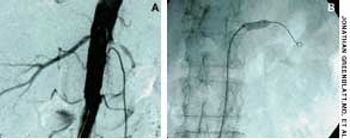

A 73-year-old man who had a history of long-standing essential hypertension, congestive heart failure, mild renal insufficiency, atrial fibrillation, and a mitral valve replacement presented with refractory hypertension. His medications included labetalol, irbesartan, and furosemide.